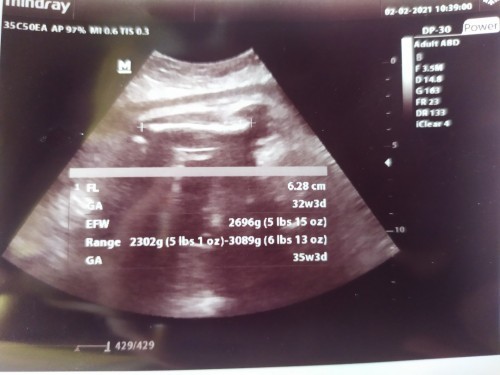

รูปนี้หมอวัดกระดูกขาค่ะ น้ำหนัก2696gค่ะเเม่ บ้านนี้หมอจะคอยบอกตลอดตอนซาวด์ว่าส่วนไหน ของลูกบ้างค่ะ